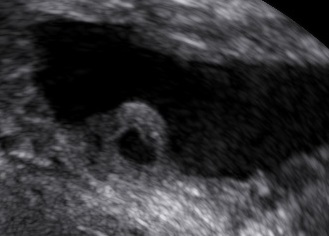

An 80-year-old female patient presents with persisting overactive bladder symptoms. After careful ultrasound examination, a unilocular cystic mass with a single urethral connecting tract containing a calculus was identified as an urethral diverticulum.

The clinician’s suspicion after acquiring a thorough patient’s history should lead to a targetted ultrasound examination combined with digital compression for possible excretion of fluid. The diagnostics may be completed with cystourethroscopy, micturating cystourethrogram, or MRI.